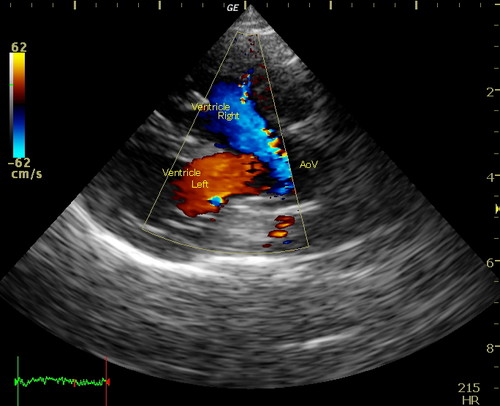

一般身体検査(聴診など)、血液検査、心電図検査、レントゲン検査、心臓エコー検査

エコー心臓・血管造影検査

心臓エコー検査・マイクロバブル造影法